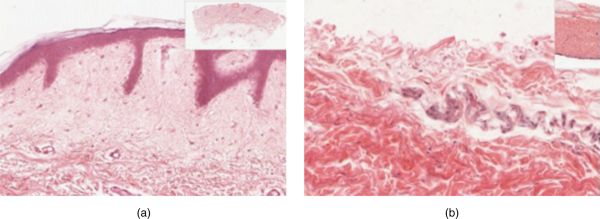

La majoria de la pell es pot classificar com a pell fina (4 capes). La pell gruixuda es troba a les palmes de les mans i les plantes dels peus, que és on hi ha una cinquena capa, anomenada estrat lúcid, que es localitza entre l’estrat corni i l’estrat granulós. Vegeu a la figura els talls transversals de l’epidermis de pell fina (a) i pell gruixuda (b), on es mostra la diferència en el gruix de la capa epitelial de la pell gruixuda.